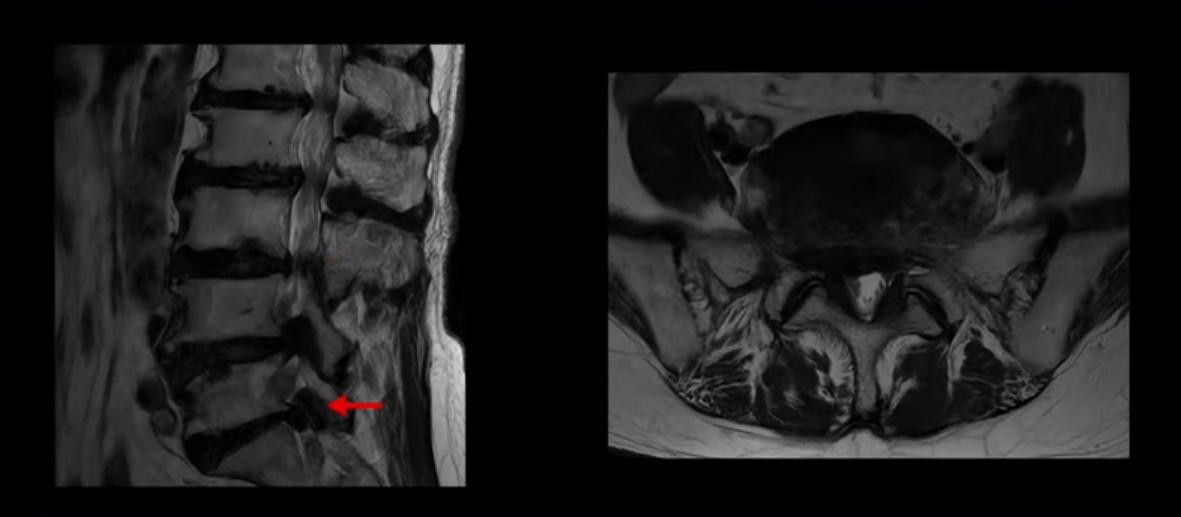

이 환자분은 MRI로 보면 허리 여러 마디가 신경이 매우 심하게 눌려 보이는 분입니다. 이분 MRI를 보면서 간단히 설명해 드린 후 어떻게 이렇게 신경이 심하게 눌린 환자분이 수술 없이 근육신경재활치료로 좋아질 수 있는지, 다리가 아파 걷지 못하는 환자가 어떻게 안 아프고 잘 걸을 수 있게 되는지, 10년 동안 괴로웠던 양 발의 시린 증상은 어떻게 사라질 수 있는지, 치료는 어떻게 하는지 자세히 설명 드리겠습니다.

MRI 보시면 (2-8) 허리의 5마디가 전부 다 심하게 퇴행되어 있습니다.

5마디 전부 다 심한 중심성 협착이 있습니다.

이렇게 모두 다 심하게 막히는 경우는 드문데요. 또한 오른쪽, 왼쪽 신경이 빠져나가는 추간공도 다 심하게 막혀있습니다.

오른쪽, 왼쪽 이렇게 신경 구멍들이 다 좁아지고 신경이 눌리니까 양쪽 다리가 발바닥까지 아파서 걷기 어렵고 양쪽 발이 10년 넘게 시린 겁니다. 당연히 수술해서 눌린 신경을 풀어줘야 한다고 들으셨는데요. 이런 환자분을 어떻게 수술 없이 치료할까요? 지금부터 설명해 드립니다.